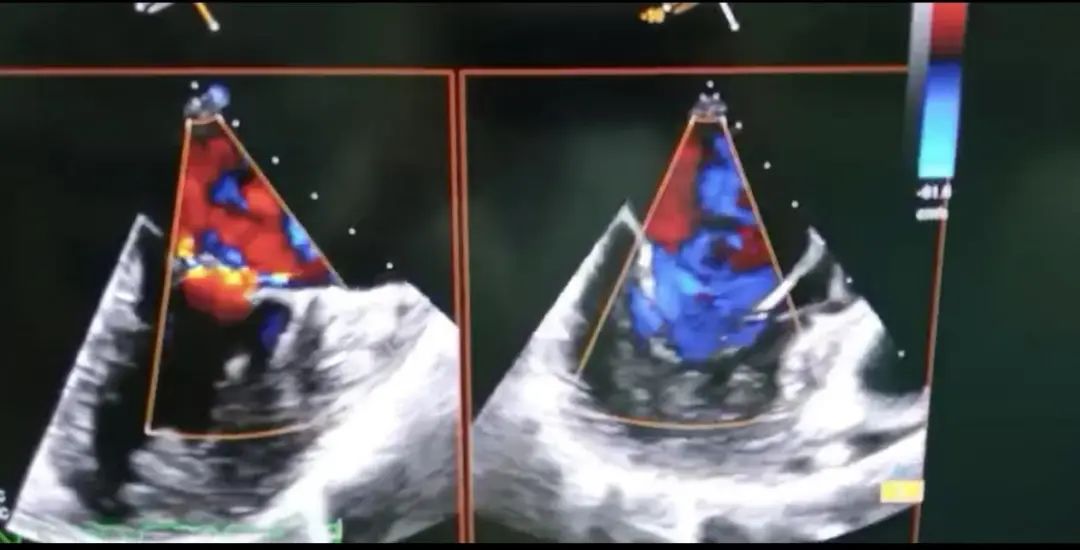

术前超声心动图

术后超声心动图